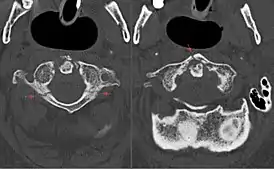

Диагностика

В диагностике переломов Джефферсона используют рентгенографию, компьютерную и магнитно-резонансную томографии. На рентгенограммах определяется смещение боковых масс атланта кнаружи[7]. Компьютерная томография даёт возможность оценить изменения костных структур, в то время как магнитно-резонансная томография — мягкотканных[8].